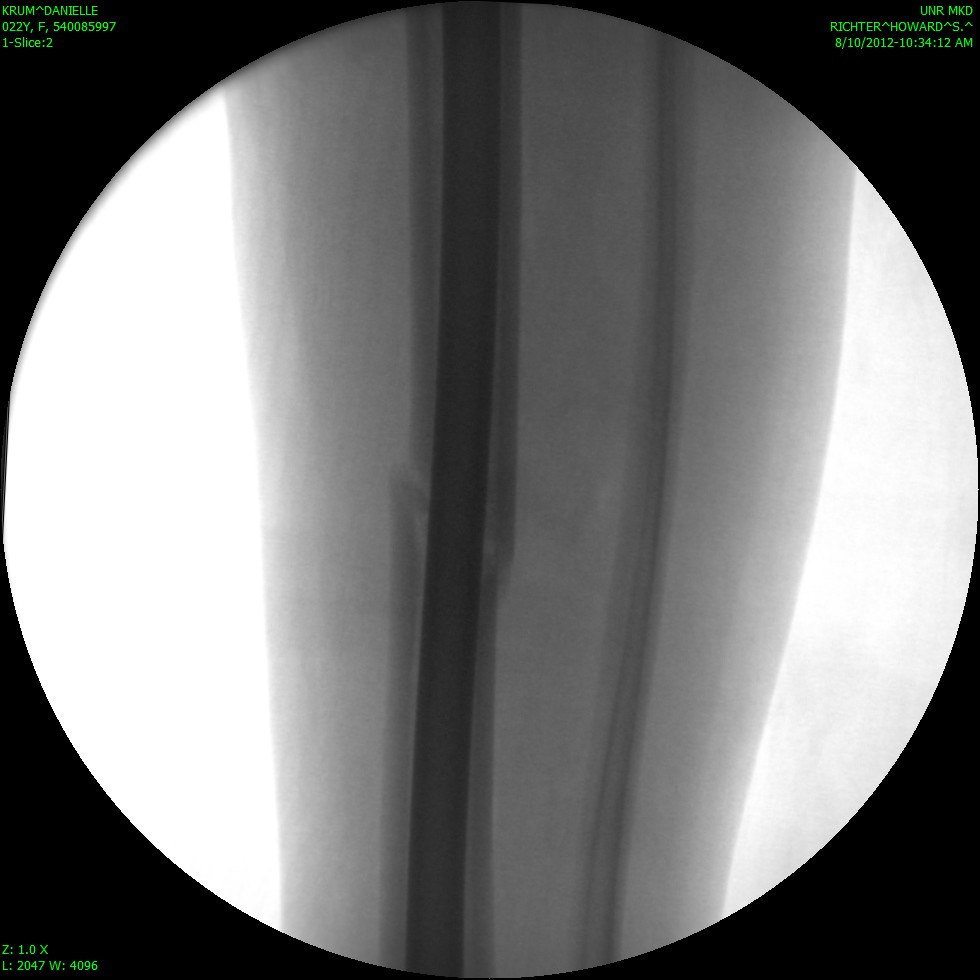

Sorry that I have been MIA for so long! I actually broke my leg on August 9th… I fractured my tibia (the big weight bearing bone in your shin) all the way through. I had the option to be in a full length cast (from my hip to my toes) for 8 weeks, or to have surgery and a rod placed so that I can walk on my leg. I chose to have surgery and now I am just going through recovery. I am working on teaching myself how to walk normal with that leg again. I am happy to be up and moving and not in a cast, but its definitely not a fun process. I have new crafts to put up soon! Some darling candy corns and a pumpkin set for the porch! I will work on getting those posted as soon as I can.

Here are some awesome pictures of my broken leg!